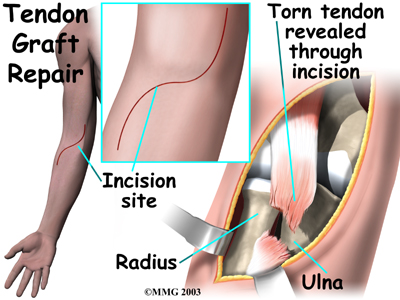

Graft Repair

If more than three or four weeks have passed since the rupture, the surgeon will usually need to make a larger incision in the front of the elbow. Also, because the tendon will have retracted further up the arm, graft tissue will be needed in order to reconnect the biceps to its original point of attachment on the radial tuberosity.

The surgeon begins by making a across the arm, just above the elbow joint. The incision curves along the front surface of the upper arm to expose the lower part of the biceps muscle.

The surface of the is removed. A burr is used to create a small cavity within the tuberosity. Several suture holes are drilled around the rim of the tuberosity.

A curved instrument is passed through the incision and directly between the radius and ulna bones. The surgeon pushes the instrument through this space, puncturing the muscles and soft tissues. The surgeon feels the back of the forearm to find the point where the instrument is protruding. A is made at this spot.

The surgeon then prepares a graft of tissue to lengthen the retracted biceps tendon. Some surgeons use a piece of hamstring tendon for the graft. Others use a section of the Achilles tendon where it attaches to the heel. This type of graft is usually an allograft, meaning that the tissue is taken from a cadaver (human tissue preserved for medical purposes).